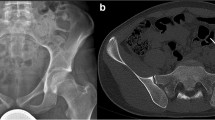

Computer navigation assistance with pelvic resection is an attractive planning tool for pelvic resection because of its ability to improve and document the accuracy of resection in the pelvis and to improve the documentation of the resected specimen and the associated margins. The surgical experience with navigation requires accurate system “registration,” reporting of surgical margins, and a comparison of local recurrence with or without the technique in order to demonstrate surgical efficacy [20]. Navigation requires documentation of the preoperative and intraoperative surgical margins that can be compared to the intraoperative and final postoperative plan and margins. Those comparisons represent important metrics for confirming the effectiveness of navigation for sarcoma resections. Demonstrating navigation accuracy with minimal radiation exposure (intraoperative CT “registration”) is another issue to be resolved by future navigation protocols for pediatric patients [1, 21, 22]. Intraoperative navigation requires the “registration” or downloading of preoperative MRI and/or CT imaging and the intraoperative “registration” of the patient to that imaging [17,18,19] (Fig. 17.3e). The use of intraoperative navigation is able to provide a “GPS” function that will improve the accuracy and planning of both surgical tumor margins and reconstructions and is particularly useful in the pelvis.

Type II pelvic Resection and reconstruction—preoperative imaging (a–c), PET scan (d), navigation margin (e), postoperative composite allograft/THR (f). (a) Preoperative pelvic X-ray. (b) Preoperative pelvic MRI (coronal T2). (c) Preoperative pelvic MRI (axial T2). (d) PET scan image of tumor. (e) 3D image of navigated pelvic procedure. (f) Postoperative Type II alloprosthetic reconstruction

Cadaveric pelvic allografts are an excellent reconstructive option for both Type I and II pelvic resections. Type III anterior, obturator resections without acetabular involvement are best managed with a Gor-Tex, allograft dermis, or other synthetic patch to reconstruct the inguinal canal and associated pelvic defect. When acetabular resection (Type II) is involved, a composite pelvic allograft and total hip reconstruction or custom implant should be considered to reconstruct the graft’s acetabulum and patient’s femoral head [23] (Fig. 17.3a–e).

Type II pelvic reconstruction can also be achieved with either custom or modular pelvic implants that incorporate a total hip reconstruction (Fig. 17.3f). Custom implants may be replaced by modular pelvic implants that incorporate sciatic notch fixation and modular acetabular components. “Saddle” prosthesis reconstruction has lost their popularity for pelvic reconstruction because of postoperative pain and instability at the “yoke”-patient osseous iliac interface [24]. While extremity sarcoma patients have been managed with “growing” implants, those implants remain associated with a high complication risk including implant aseptic loosening, sepsis, and failure of lengthening. There are significant limits regarding how large a segment these devices can lengthen (4–6 cm), and their use in the pelvis and hip joint is extremely limited. Flail reconstructions are a reasonable option for patients with large tumors and have demonstrated surprisingly good function postoperatively, and pelvic amputations should always be considered as a possible surgical option, especially in patients with large or recurrent tumors [5].

Type I and Type II pelvic allografts should be fixed to the remaining adjacent pelvis with plate and screw fixation at both the anterior pubic and posterior iliac osteosynthesis sites (Fig. 17.3f). That fixation should include at least six cortices of fixation at both host junction sites. Additional sacroiliac fixation should include two or three carefully placed large diameter sacroiliac screws if the graft involves the sacroiliac joint. If radiographic evidence of bony healing is not apparent on radiographs/CT imaging at the osseous junction site at 10–12 months postoperatively, fixation revision and autogenous bone grafting should be considered as an additional procedure [25,26,27]. Initial selection of pelvic allografts for reconstruction should be selected with consideration of patient and donor gender, age, and acetabular diameter. Pelvic allograft sizing can be achieved by the assessment of acetabular diameter for both the donor graft and, if possible, patient gender and age of grafts versus patients should be considered with graft selection [28]. Pelvic allografts carry a risk of postoperative infection but can achieve bony union at the host bone-graft interface and may offer better soft tissue attachment.